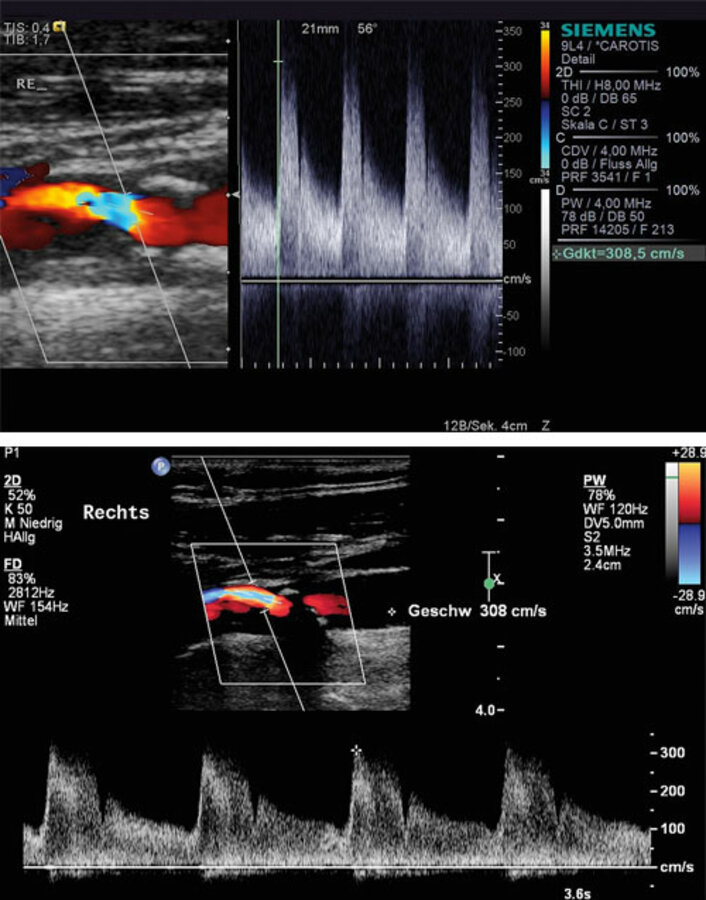

Longitudinale (links) und transversale (rechts) Einstellung einer nicht-stenosierenden Plaque. Die jeweils größte messbare Dicke gilt als Maß für die Verlaufskontrollen. Longitudinale (links) und transversale (rechts) Einstellung einer nicht-stenosierenden Plaque. Die jeweils größte messbare Dicke gilt als Maß für die Verlaufskontrollen. © Arning C. Hamburger Ärzteblatt 2023; 77: 28–30 © Hamburger Ärzteverlag, Hamburg